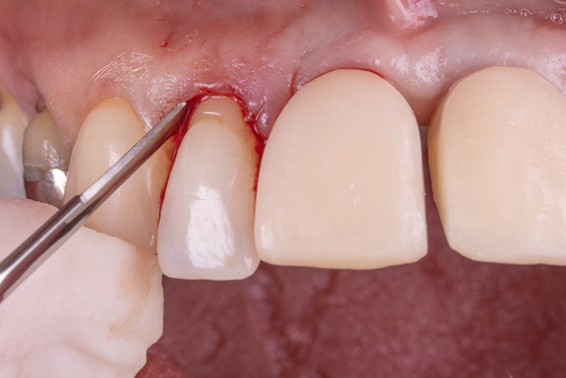

Exodontia atraumática dos elementos 12 e 22, com uso de periótomo e fórceps, instalação imediata do implante Cone Morse “Due Cone” Implacil 3.5×11. Para perfuração inicial, foi utilizada a técnica do approach palatino e, ao final do processo de fresagem e instalação, obteve-se uma carga primária de 45 newtons, a qual nos permitiu ter segurança para instalação do pilar Ideale, com medida 3.5×3.5×4.